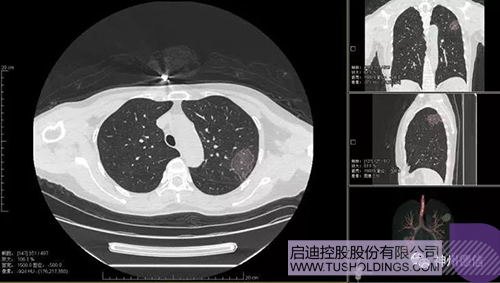

神州德信新冠肺炎檢測及智能量化分析系統

啟迪戰略投資企業神州德信作為國內領先的肺部影像人工智能企業,針對新型冠狀病毒肺炎開發了智能檢測及量化分析系統,并在陜西、重慶等地定點醫院投入使用。該系統在疑似病例大規模快速篩查及精準診斷方面發揮了重要作用,特別是其具有的肺炎患者臨床影像跟蹤量化隨訪功能,為快速有效阻斷疫情擴散提供了有力武器。